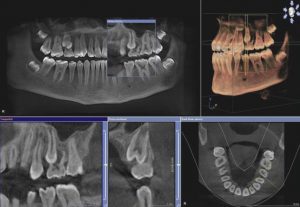

Стоматологическая 3-D томограграфия

Использование технологии конусного луча 3-D позволяет стоматологам визуализировать область головы или черепа в третьем измерении. Хотя трехмерная конусно-лучевая технология важна, она не заменяет и не сводит на нет необходимость в ценной, но ограниченной двухмерной рентгенографии. Эта новая технология предоставляет еще один инструмент, помогающий практикующим врачам улучшить их основанный на фактических данных подход к стоматологическому лечению и планированию лечения.

Внедрение этой технологии позволяет дополнительно визуализировать рассматриваемые области, предоставляя при этом больше данных, позволяющих лучше понять и интерпретировать варианты стоматологического лечения. Использование этой технологии выходит далеко за рамки традиционных методов диагностики. Можно создавать виртуальные челюстно-лицевые модели пациента, чтобы его зубную анатомию можно было реконструировать, просматривать и исследовать в нескольких плоскостях. С этими дополнительными данными стоматологи могут практиковать виртуальную хирургию до того, как будет оказано какое-либо стоматологическое лечение.

Одно сканирование может захватить всю челюсть с достаточным полем зрения (FOV), чтобы обеспечить наилучшее изображение с наименьшим количеством лучевой нагрузки. С помощью этого сканирования врач может лучше измерить твердые ткани или толщину костей, а также увидеть мягкие ткани и найти нервные каналы. Этот дополнительный инструмент предоставляет еще один способ помочь пациенту поставить более четкий и точный диагноз и спланировать лечение в дополнение к более точному прогнозированию успеха лечения.